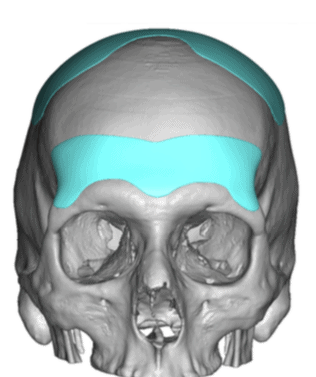

Patient 28

Desire for rounder shape to the top of the head from a congenital parasagittal deficiency skull shape.

Custom skull implant designed to fill in the parasagittal deficiencies.

Desire for rounder shape to the top of the head from a congenital parasagittal deficiency skull shape.

Custom skull implant designed to fill in the parasagittal deficiencies.